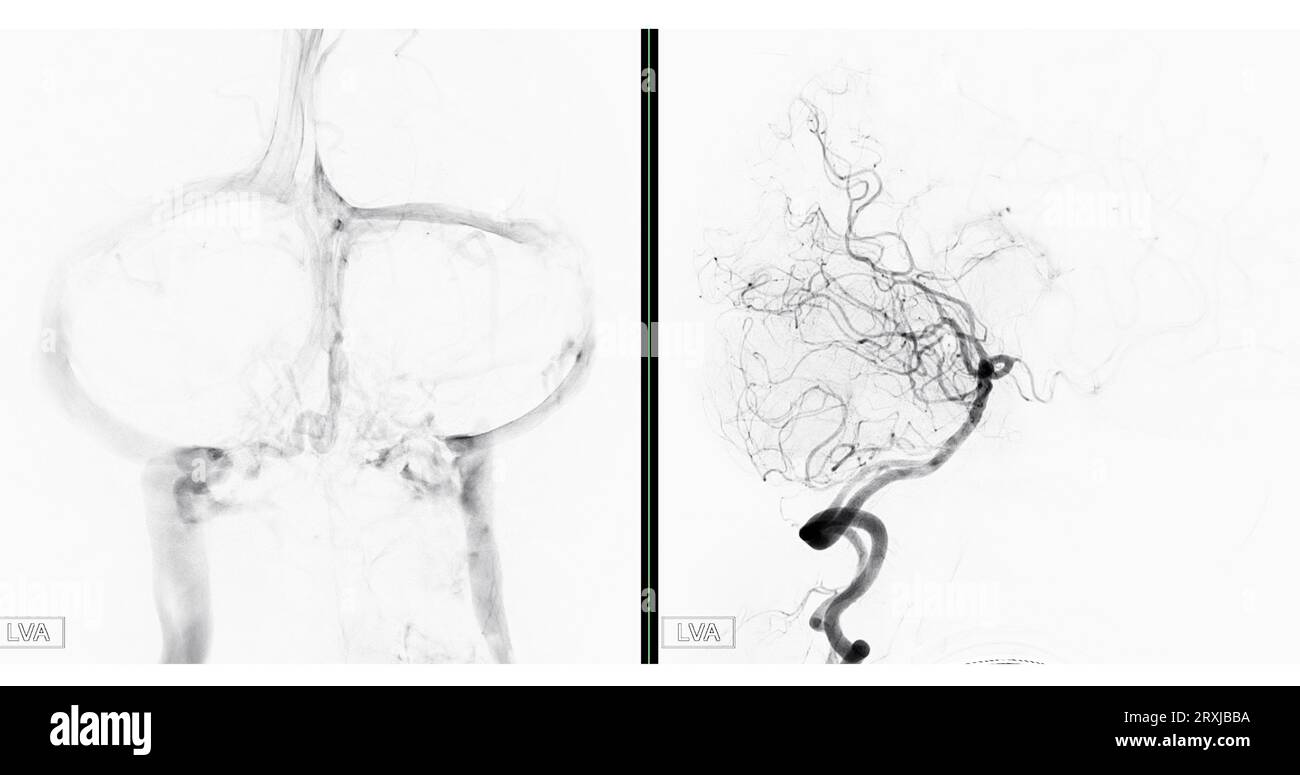

Fluoroscopy Intervention Radiology Image Revealing Cerebral Artery Fluoro Hysterogram The test may be done to look for the cause of. Check for a blocked fallopian tube. a hysterosalpingogram (hsg) is done to: a hysterosalpingogram (hsg) is a fluoroscopic examination of the uterus and the fallopian tubes, most commonly used in. a hysterosalpingogram is a diagnostic imaging modality primarily utilized in assessing female infertility. What is a. Fluoro Hysterogram.

Cerebral angiography image from Fluoroscopy in intervention radiology Fluoro Hysterogram a hysterosalpingogram is a diagnostic imaging modality primarily utilized in assessing female infertility. The test may be done to look for the cause of. hysterosalpingography (hsg) is an outpatient fluoroscopy procedure that evaluates the uterine cavity and fallopian. a hysterosalpingogram (hsg) is a fluoroscopic examination of the uterus and the fallopian tubes, most commonly used in. Check. Fluoro Hysterogram.

Cerebral angiography image from Fluoroscopy in intervention radiology Fluoro Hysterogram a hysterosalpingogram is a diagnostic imaging modality primarily utilized in assessing female infertility. a hysterosalpingogram (hsg) is done to: What is a hysterosalpingogram (hsg)? Check for a blocked fallopian tube. a hysterosalpingogram (hsg) is a fluoroscopic examination of the uterus and the fallopian tubes, most commonly used in. The test may be done to look for the. Fluoro Hysterogram.